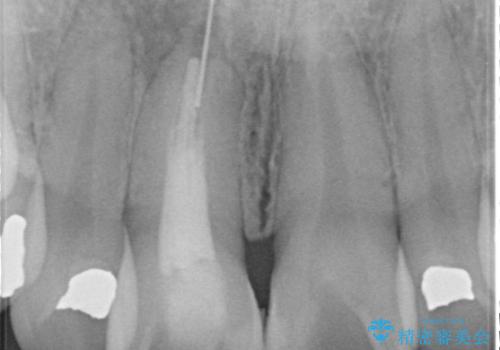

お痛みは無く、たまに異和感があるとのことでレントゲン撮影をすると、以前根の治療をされた際の器具が破折したまま残っていました。

破折した器具を除去したのち、根管治療、ファイバーコア築造、セラミッククラウンの製作を行いました。